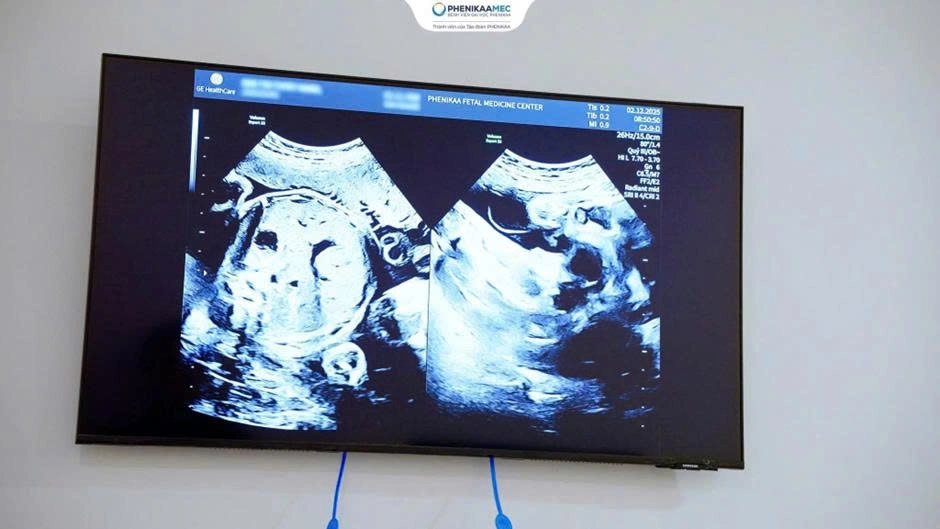

Một trong những điểm nổi bật của phòng khám là việc áp dụng quy trình siêu âm theo chuẩn ISUOG (Hiệp hội Siêu âm Sản phụ khoa Quốc tế), ứng dụng máy siêu âm GE Voluson Expert 22 hiện đại bậc nhất thế giới, cho phép phát hiện sớm các biến chứng nguy hiểm như hội chứng truyền máu song thai (TTTS), chậm tăng trưởng bất đối xứng, song thai tiêu biến, song thai dính nhau hay các bất thường liên quan đến dây rốn. Ngay từ giai đoạn sớm của thai kỳ (tuần 11-14), bác sĩ sẽ xác định chính xác loại song thai (một bánh nhau hay hai bánh nhau) - yếu tố then chốt giúp tiên lượng nguy cơ và xây dựng chiến lược theo dõi phù hợp cho từng trường hợp. Bên cạnh đó, sự phát triển của từng thai nhi được theo dõi một cách độc lập và chi tiết thông qua 42 chỉ số như cân nặng, tốc độ tăng trưởng, lượng nước ối,… đảm bảo kiểm soát toàn diện thai kỳ và phát hiện sớm những dấu hiệu bất thường dù là nhỏ nhất. Thông qua kết quả thăm khám, mẹ bầu sẽ được tư vấn chuyên sâu và xây dựng kế hoạch chăm sóc cá thể hóa theo từng giai đoạn của thai kỳ song thai. Nhờ đó, nguy cơ sinh non, tiền sản giật và các biến chứng chu sinh được giảm thiểu đáng kể.

Hình ảnh siêu âm cho thấy thai phụ mang song thai kèm đa ối và rau tiền đạo trung tâm cần được theo dõi sát trong giai đoạn cuối thai kỳ